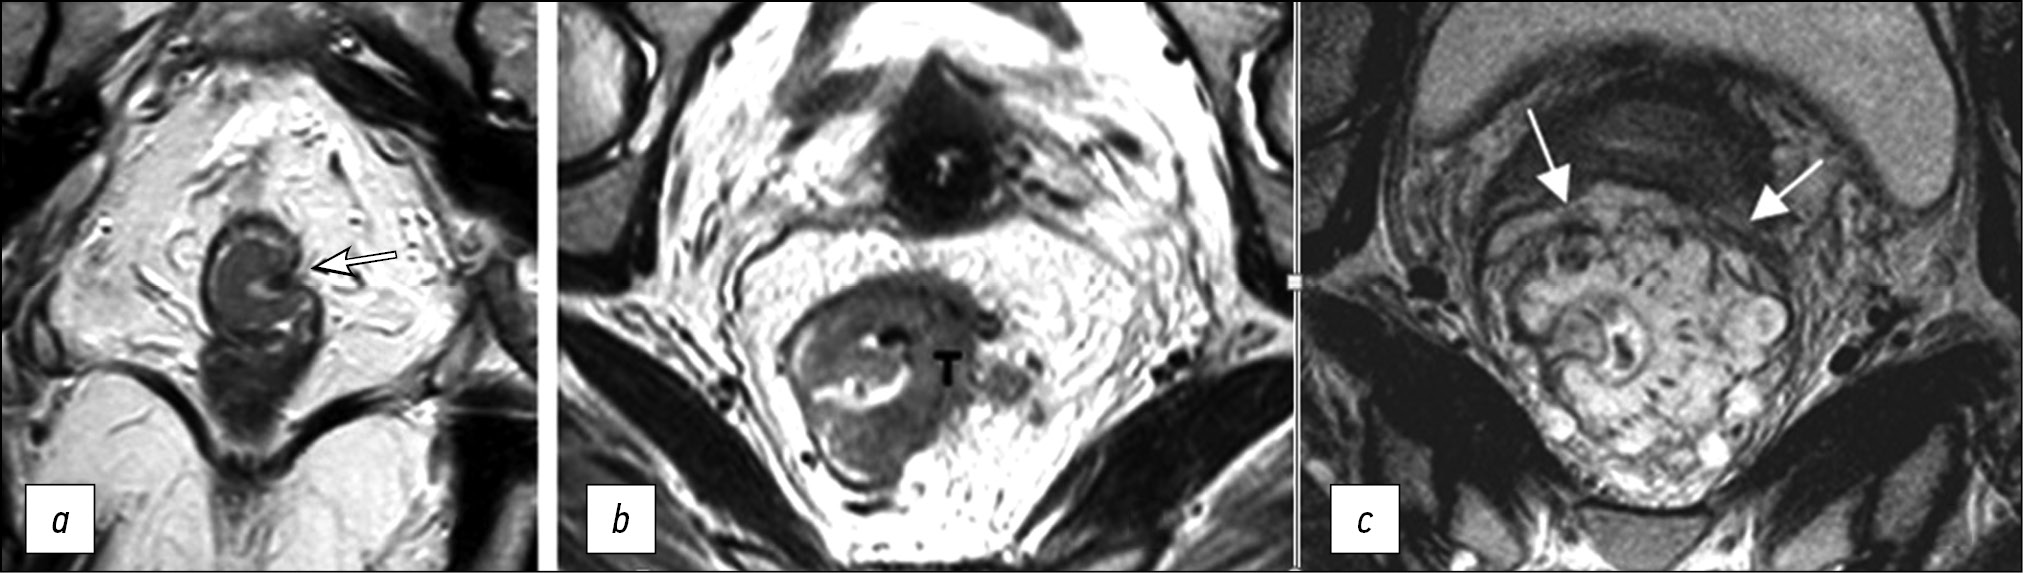

The depth of extramural invasion is the maximum distance from the outer edge of the muscular layer of the wall at the base of the extramural component of the primary tumor to its outer edge, as observed on high-resolution T2-WI oriented perpendicular to the intestinal wall at the level of the tumor (Fig. 2). The depth of extramural invasion is used to determine the substage of T3 tumors.

Fig. 2. Circular border (edge) of rectal resection during total mesorectumectomy. (a) Diagram showing extramural growth of the tumor (green line); mesorectal fascia (yellow line); circular border (edge) of resection (red line); distance from the tumor to the mesorectal fascia (double black arrow); distance from the tumor to the circular border (edge) of resection (double red arrow). (b) T2-weighted images in the coronal plane of the tumor of the lower ampullary part of the rectum with extramural vascular invasion and deposit at the level of axial T2-weighted images. (c) Upper axial section corresponds to the level of the deposit involving the mesorectal fascia (black arrows), extramesorectal lymph node (dotted arrow). The lower axial section corresponds to the level of extramural vascular invasion. The depth of extramural invasion (a double white arrow). The distance from the tumor to the elevator muscle of anus (a double black arrow).

The status of CRM is determined by histological examination of the surgically removed rectum specimens. It can be predicted based on MRI by the shortest distance between the extramural component of the tumor/deposit/affected lymph node and the mesorectal fascia. Involvement of the CRM is indicated as CRM(+) if this distance is ≤1 mm. For low-lying rectal cancer, the shortest distance is determined to the elevator muscle of anus. The distance from enlarged lymph nodes without signs of extracapsular spread (with smooth contours) is not considered and should be regarded as CRM(−) [13].

Extramural vascular/venous invasion in histological examination represents intravascular growth of the tumor beyond the rectal wall, serving as a predictor of poor prognosis, lymphatic and distant metastases, and tumor recurrence [14–17]. On T2-WI, extramural vascular/venous invasion is characterized by the spread of a tumor signal into the vascular structures of the mesorectal tissue [6, 18, 19], which can be combined with the increased diameter of the affected vessel or with the tumor extending beyond its walls with the formation of a node, beaded, or worm-like structure. It is important to note that the MRI assessment of extramural venous invasion in vessels less than 3 mm in diameter is unreliable. When determining the category “T” (T3 and T4 tumors) in cases of fusion of the primary tumor and an extramural venous invasion lesion, their total size should be considered.

Mucinous cancer is a prognostically unfavorable histological variant of rectal cancer with tumor content of extracellular mucin >50% of the tumor volume. On MRI, mucin accumulations have a hyperintense signal on T2-WI (Fig. 3).

Fig. 3. Variants of tumor image on T2-WI. (a) Polypoid/exophytic tumor (arrow). (b) Semicircular tumor (T), extramural vascular invasion (arrows). (c) Mucinous tumor (arrows).

Polypoid tumor is a tumor with an exophytic type of growth (Fig. 3). It may have a pedicle with clearly visible feeding vessels. The location of such a tumor can be indicated using a conventional dial (12 o’clock for the center of the anterior wall, 6 o’clock for the center of the posterior wall, 3 o’clock for the center of the left wall, and 9 o’clock for the center of the right wall).

Circular/subcircular tumor spreads over the entire or almost entire circumference of the rectal lumen (Fig. 3).